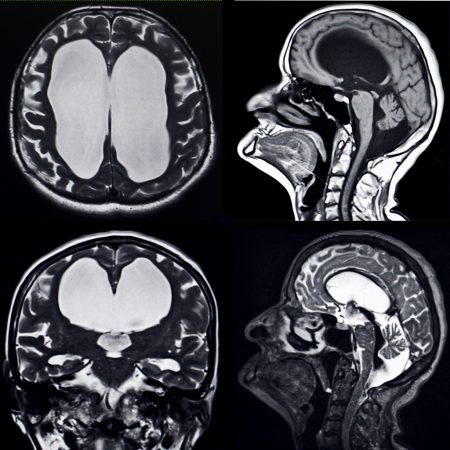

Normal pressure hydrocephalus (NPH) is a progressive condition that occurs when there is too much cerebrospinal fluid (CSF) in the brain. Normally, CSF is produced inside two large cavities in the brain called ventricles. NPH occurs when the normal volume of CSF is not absorbed fast enough, causing the fluid to collect in the ventricles.

As CSF slowly builds up in the ventricles, they enlarge and stretch the brain. This can damage nearby nerve fibers that control the legs, bladder, and memory. NPH can be hard to diagnose because it can resemble other, more common causes of dementia or Parkinson’s. If diagnosed early, NPH can be treated with a shunt device that drains the excess fluid and reverses some of the symptoms.

• A computed tomography (CT) or magnetic resonance imaging (MRI) scan is ordered to look for enlarged ventricles or other signs of blockage. If the scan is normal, the patient does not have NPH.